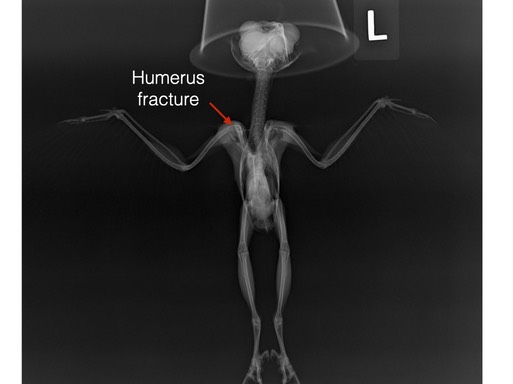

Northern Saw-whet Owl 21-003 died shortly we had completed our initial exam and treatment. The tiny owl was quite thin, weighing just 55 grams (less than two ounces) and had a fractured right humerus with significant chest trauma and internal hemorrhaging.